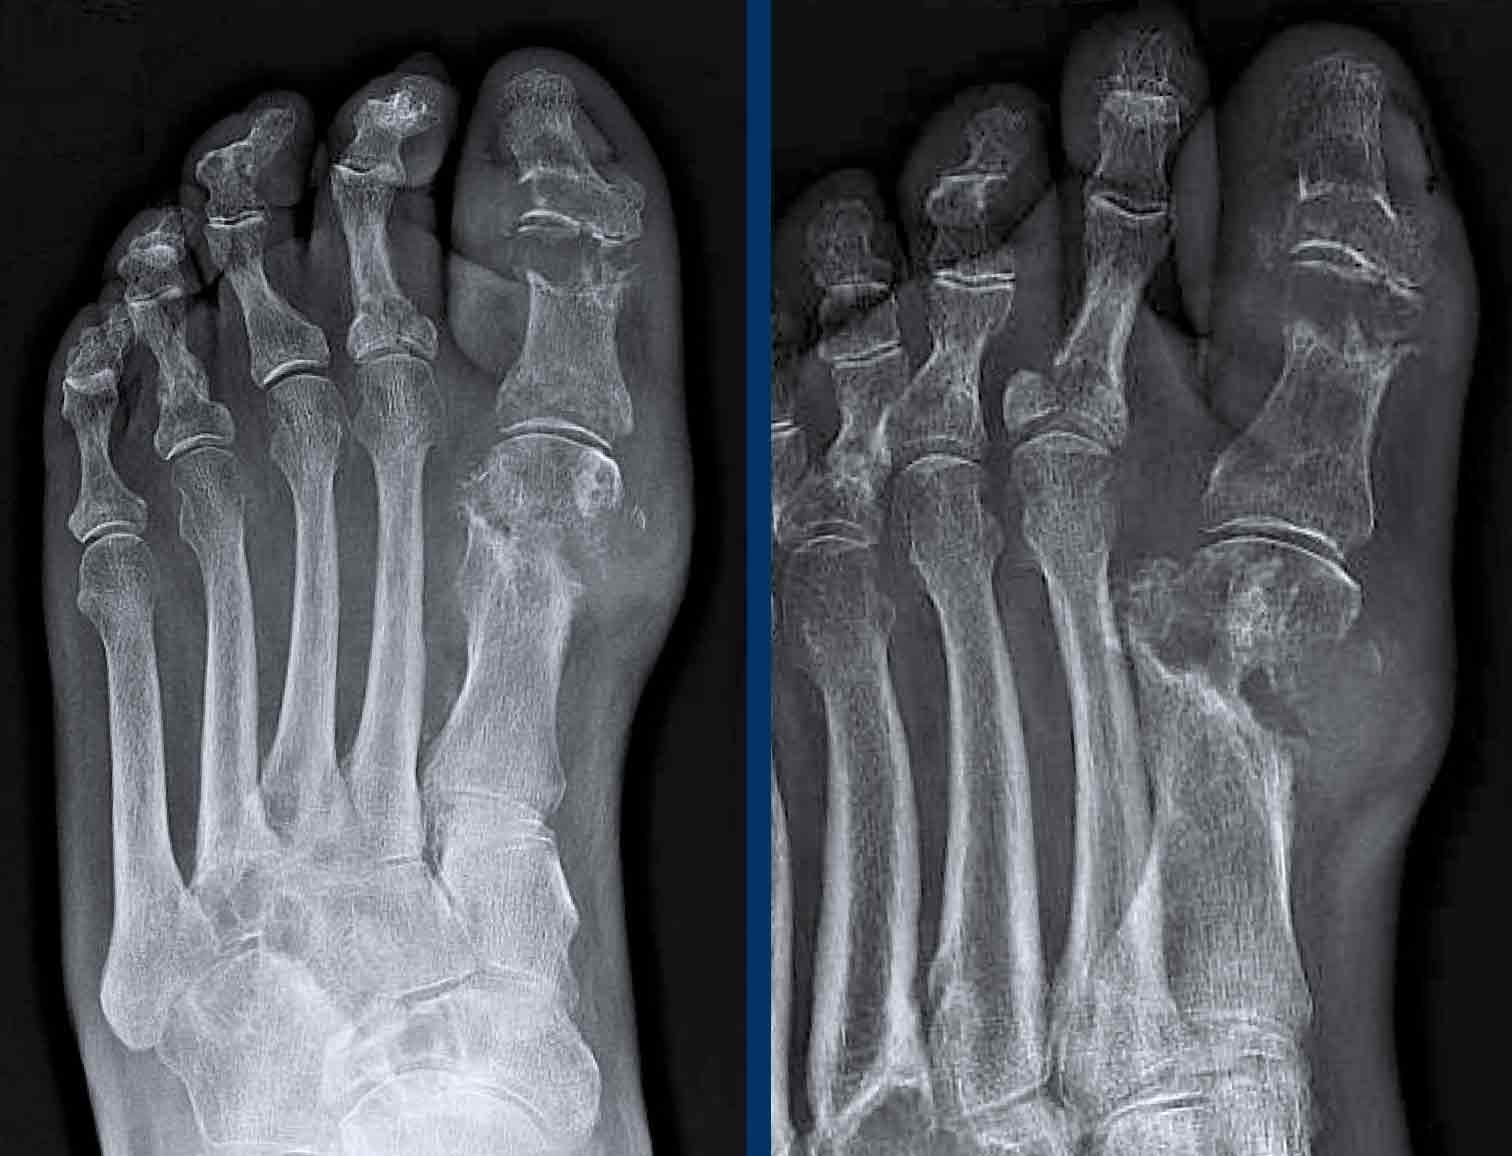

Biến dạng bút chì trong cốc

A. Biến dạng bút chì trong cốc tại ngón chân thứ 1 và thứ 5.

B. Tiêu xương đầu ngón (acro-osteolysis) với tiêu xương chỏm đốt ngón xa của ngón 2-4 và 5.

Có bào mòn xương tại khớp bàn ngón chân (MTP) 2 và 3.

Viêm màng xương trong viêm khớp vảy nến

Đây là bệnh nhân viêm khớp vảy nến.

Lưu ý hình ảnh viêm màng xương mờ nhạt tại đốt ngón xa của ngón 1 bên phải (đầu mũi tên).

Có các bào mòn xương nhỏ tại chỏm đốt ngón xa của ngón 2 và 3 bên trái (mũi tên trắng).